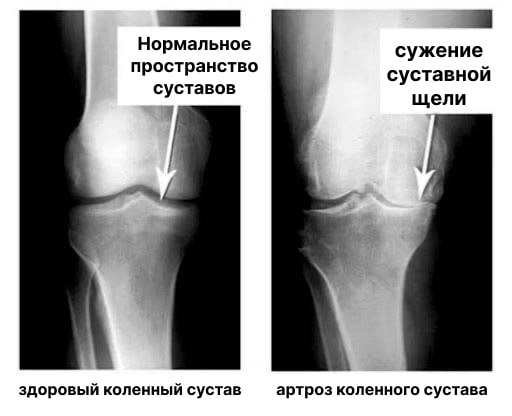

Заседналият начин на живот, стресът, излишъкът от сол и захар в храната — всичко това омекотява хрущялната тъкан, износва я и я изтънява. С всяко ново движение хрущялът се износва и деформира, костите започват да се трият една в друга, причинявайки непоносима болка.

Ревматоидният артрит и остеоартритът могат да доведат до инвалидност след 3-5 години от началото на заболяването и могат да съкратят продължителността на живота на пациентите с 15-20 години!

Не се шегувайте с артроза и артрита! Заболяванията на ставите ще ви доведат до инвалидна количка за по-малко от 3 години!